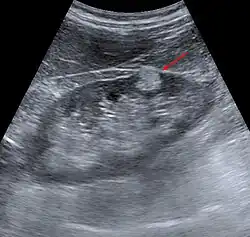

- Im Ultraschall finden sich durch den Fettgehalt stark echogene Raumforderungen in der Niere.